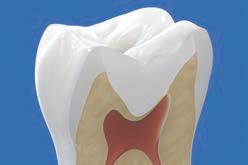

PROCEDURE

dentin) with slow-speed round bur or excavator. To control overexcavating near the pulp, remove final portion of caries with hand excavator.